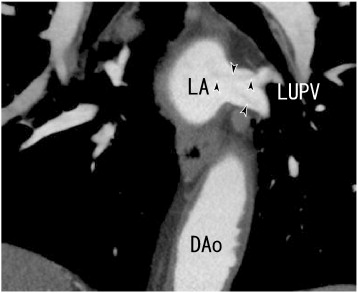

A 64-MDCT scan showed coronal images of thrombi in the LUPV (arrowheads). DAo: ...

Fig. 2.

A 64-MDCT scan showed coronal images of thrombi in the LUPV (arrowheads). DAo: descending aorta, LA: left atrium, and LUPV: left upper pulmonary vein.